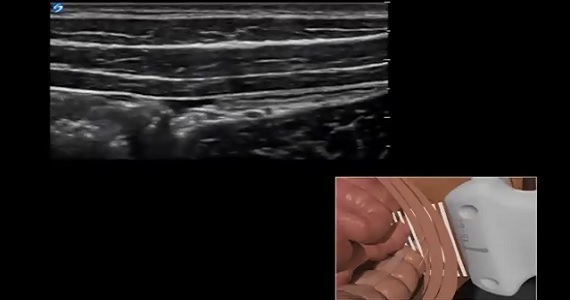

View 3D and scanning technique videos of various anesthetic nerve blocks that are outside the scope of the anesthesia courses on the Sonosite Institute.